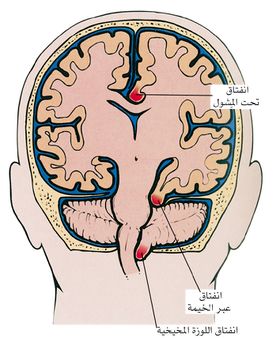

الشكل (1) انفتاق النسيج الدماغي

ـ الانفتاق تحت المشول :subfalcine herniation يحدث عندما يؤدي توسع أحد نصفي الكرة المخية إلى اندفاع التلفيف الحزامي cingulate gyrus وانحشاره تحت مشول منجل المخ falx cerebri (وهذا الأخير هو أحد الحواجز الصلبة المذكورة أعلاه). وكثيراً ما يترافق ذلك بانضغاط فروع الشريان المخي الأمامي، ولأن هذا الشريان يروي المنطقة من الدماغ المسؤولة عن حركة الطرف السفلي المقابل، فإن هذا الانفتاق يترافق عادة مع حدوث ضعف في الطرف السفلي.

ـ الانفتاق عبر الخيمة transtentorial herniation (أو الانفتاق المحجني uncal herniation): يحدث عندما ينضغط الجزء الأنسي من الفص الصدغي على الحافة الحرة للخيمة المخيخية. ينتج من ذلك انضغاط العصب الثالث المحرك للعين مما يسبب توسع الحدقة واضطراباً في حركات العين في ذلك الجانب. وكثيراً ما ينضغط الشريان المخي الخلفي مما يؤدي إلى اضطرابات معينة في الرؤية، وقد تحدث في مراحل متقدمة من الإصابة آفات نزفية في جذع الدماغ.

ـ انفتاق اللوزة المخيخية :tonsillar herniation المقصود به انزياح اللوزتين المخيخيتين وهبوطهما عبر الثقبة الكبرى (وهي فتحة كبيرة في أسفل الجمجمة). يحمل هذا الانفتاق خطورة كبيرة على الحياة لأنه يؤدي إلى انضغاط جذع الدماغ وإصابة مراكز التنفس في البصلة السيسائية.